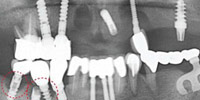

老年人由于口腔疾病的困扰,导致很多人都有牙齿脱落的情况。那么,老年人牙齿脱落后应该怎么办呢?对此,我们来听听康贝佳口腔医院医生怎么说。 三种牙齿缺失修复示意图 老年人牙齿脱...[详细]2016-12-23 阅读:

可选方法:种植牙(单颗缺失、多颗缺失及多各牙缺失)、All-on-4种植牙(半/全口牙缺失)、烤瓷牙(个别牙缺失)、活动义齿(全部牙缺失类型)

种植牙(单颗缺失、多颗缺失及多各牙缺失)

All-on-4种植牙(半/全口牙缺失)

烤瓷牙(个别牙缺失)

活动义齿(全部牙缺失类型)